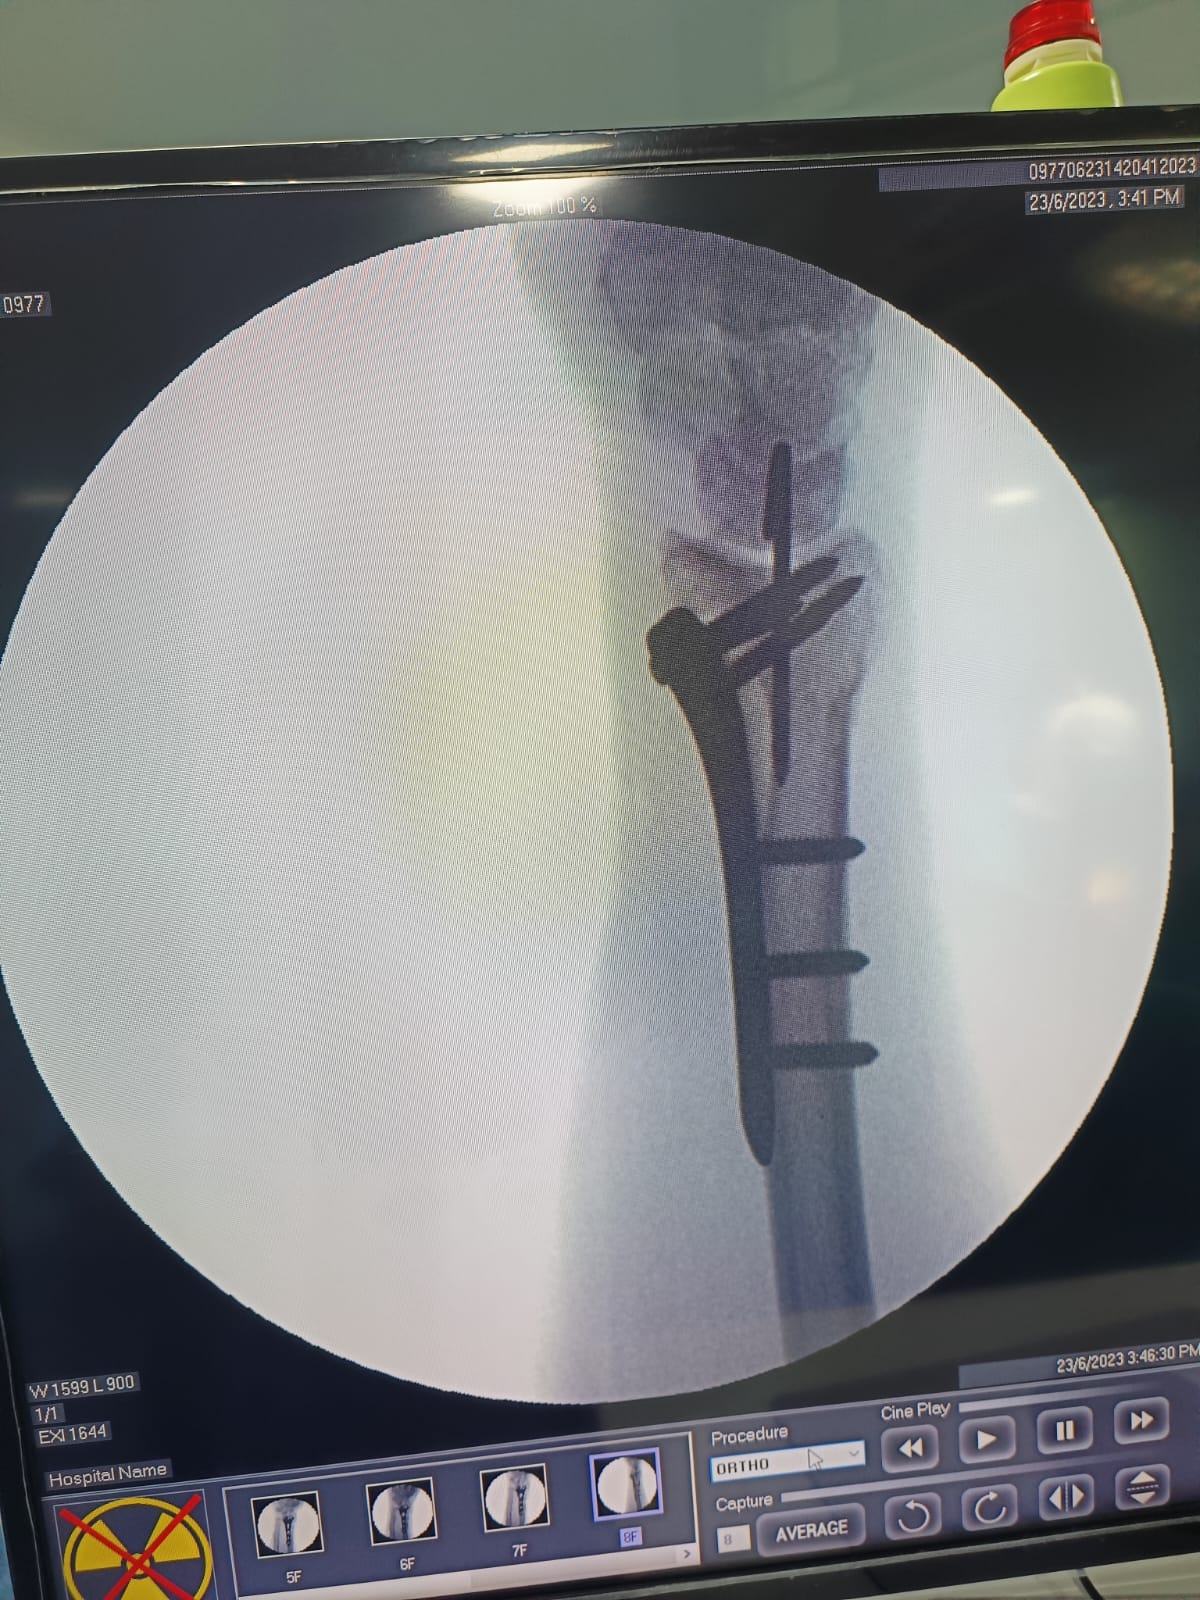

Fracture and Trauma Surgery

Arthroscopic Surgery

Gallery